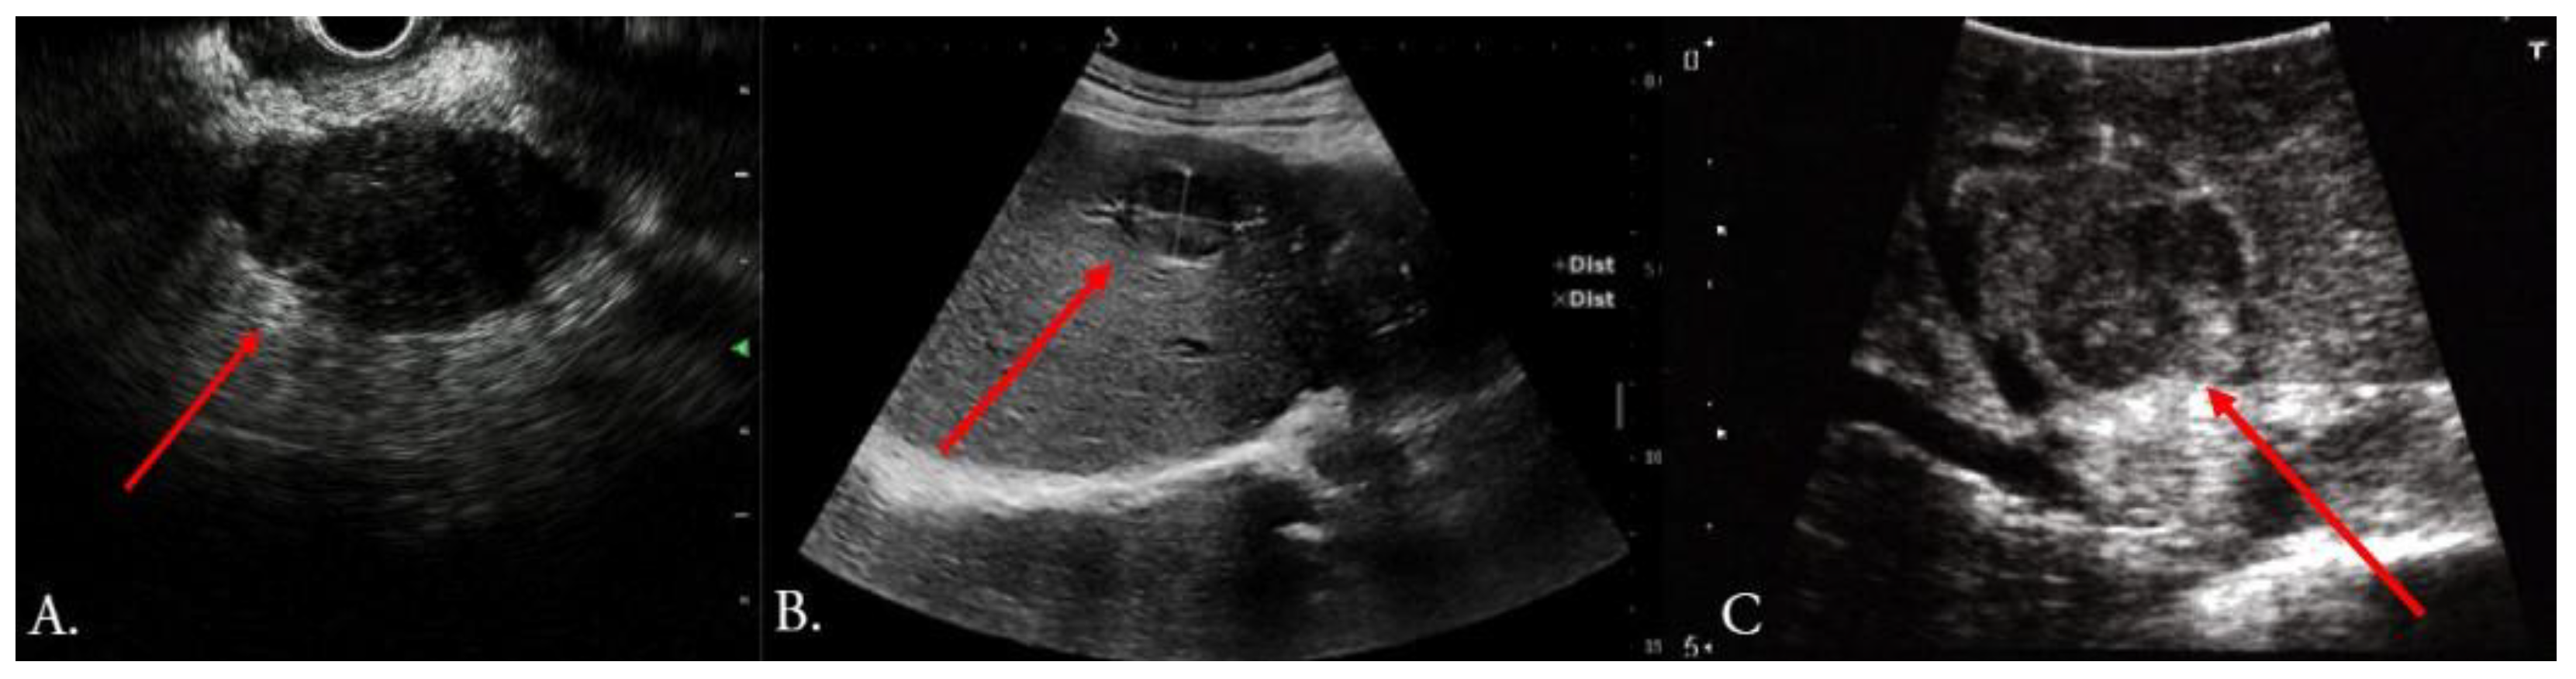

- Bartos, A.; Iancu, I.; Ciobanu, L.; Badea, R.; Sparchez, Z.; Bartos, D.M. Intraoperative ultrasound in liver and pancreatic surgery. Med. Ultrason. 2021, 23, 319–328. [Google Scholar] [CrossRef] [PubMed]

- Sietses, C.; Meijerink, M.R.; Meijer, S.; van den Tol, M.P. The impact of intraoperative ultrasonography on the surgical treatment of patients with colorectal liver metastases. Surg. Endosc. 2010, 24, 1917–1922. [Google Scholar] [CrossRef]

- Hoch, G.; Croise-Laurent, V.; Germain, A.; Brunaud, L.; Bresler, L.; Ayav, A. Is intraoperative ultrasound still useful for the detection of colorectal cancer liver metastases? HPB 2015, 17, 514–519. [Google Scholar] [CrossRef] [PubMed]

- Torzilli, G.; Montorsi, M.; Donadon, M.; Palmisano, A.; Del Fabbro, D.; Gambetti, A.; Olivari, N.; Makuuchi, M. “Radical but conservative” is the main goal for ultrasonography-guided liver resection: Prospective validation of this approach. J. Am. Coll. Surg. 2005, 201, 517–528. [Google Scholar] [CrossRef]

- Sahani, D.V.; Kalva, S.P.; Tanabe, K.K.; Hayat, S.M.; O’Neill, M.J.; Halpern, E.F.; Saini, S.; Mueller, P.R. Intraoperative US in patients undergoing surgery for liver neoplasms: Comparison with MR imaging. Radiology 2004, 232, 810–814. [Google Scholar] [CrossRef]

- Torzilli, G.; Del Fabbro, D.; Palmisano, A.; Donadon, M.; Bianchi, P.; Roncalli, M.; Balzarini, L.; Montorsi, M. Contrast-enhanced intraoperative ultrasonography during hepatectomies for colorectal cancer liver metastases. J. Gastrointest. Surg. 2005, 9, 1148–1153; discussion 1153–1144. [Google Scholar] [CrossRef]

- Shah, A.J.; Callaway, M.; Thomas, M.G.; Finch-Jones, M.D. Contrast-enhanced intraoperative ultrasound improves detection of liver metastases during surgery for primary colorectal cancer. HPB 2010, 12, 181–187. [Google Scholar] [CrossRef]

- Peloso, A.; Franchi, E.; Canepa, M.C.; Barbieri, L.; Briani, L.; Ferrario, J.; Bianco, C.; Quaretti, P.; Brugnatelli, S.; Dionigi, P.; et al. Combined use of intraoperative ultrasound and indocyanine green fluorescence imaging to detect liver metastases from colorectal cancer. HPB 2013, 15, 928–934. [Google Scholar] [CrossRef] [PubMed]

- van der Steen, K.; Bosscha, K.; Lips, D.J. The value of laparoscopic intraoperative ultrasound of the liver by the surgeon. Ann. Laparosc. Endosc. Surg. 2021, 6, 17. [Google Scholar] [CrossRef]